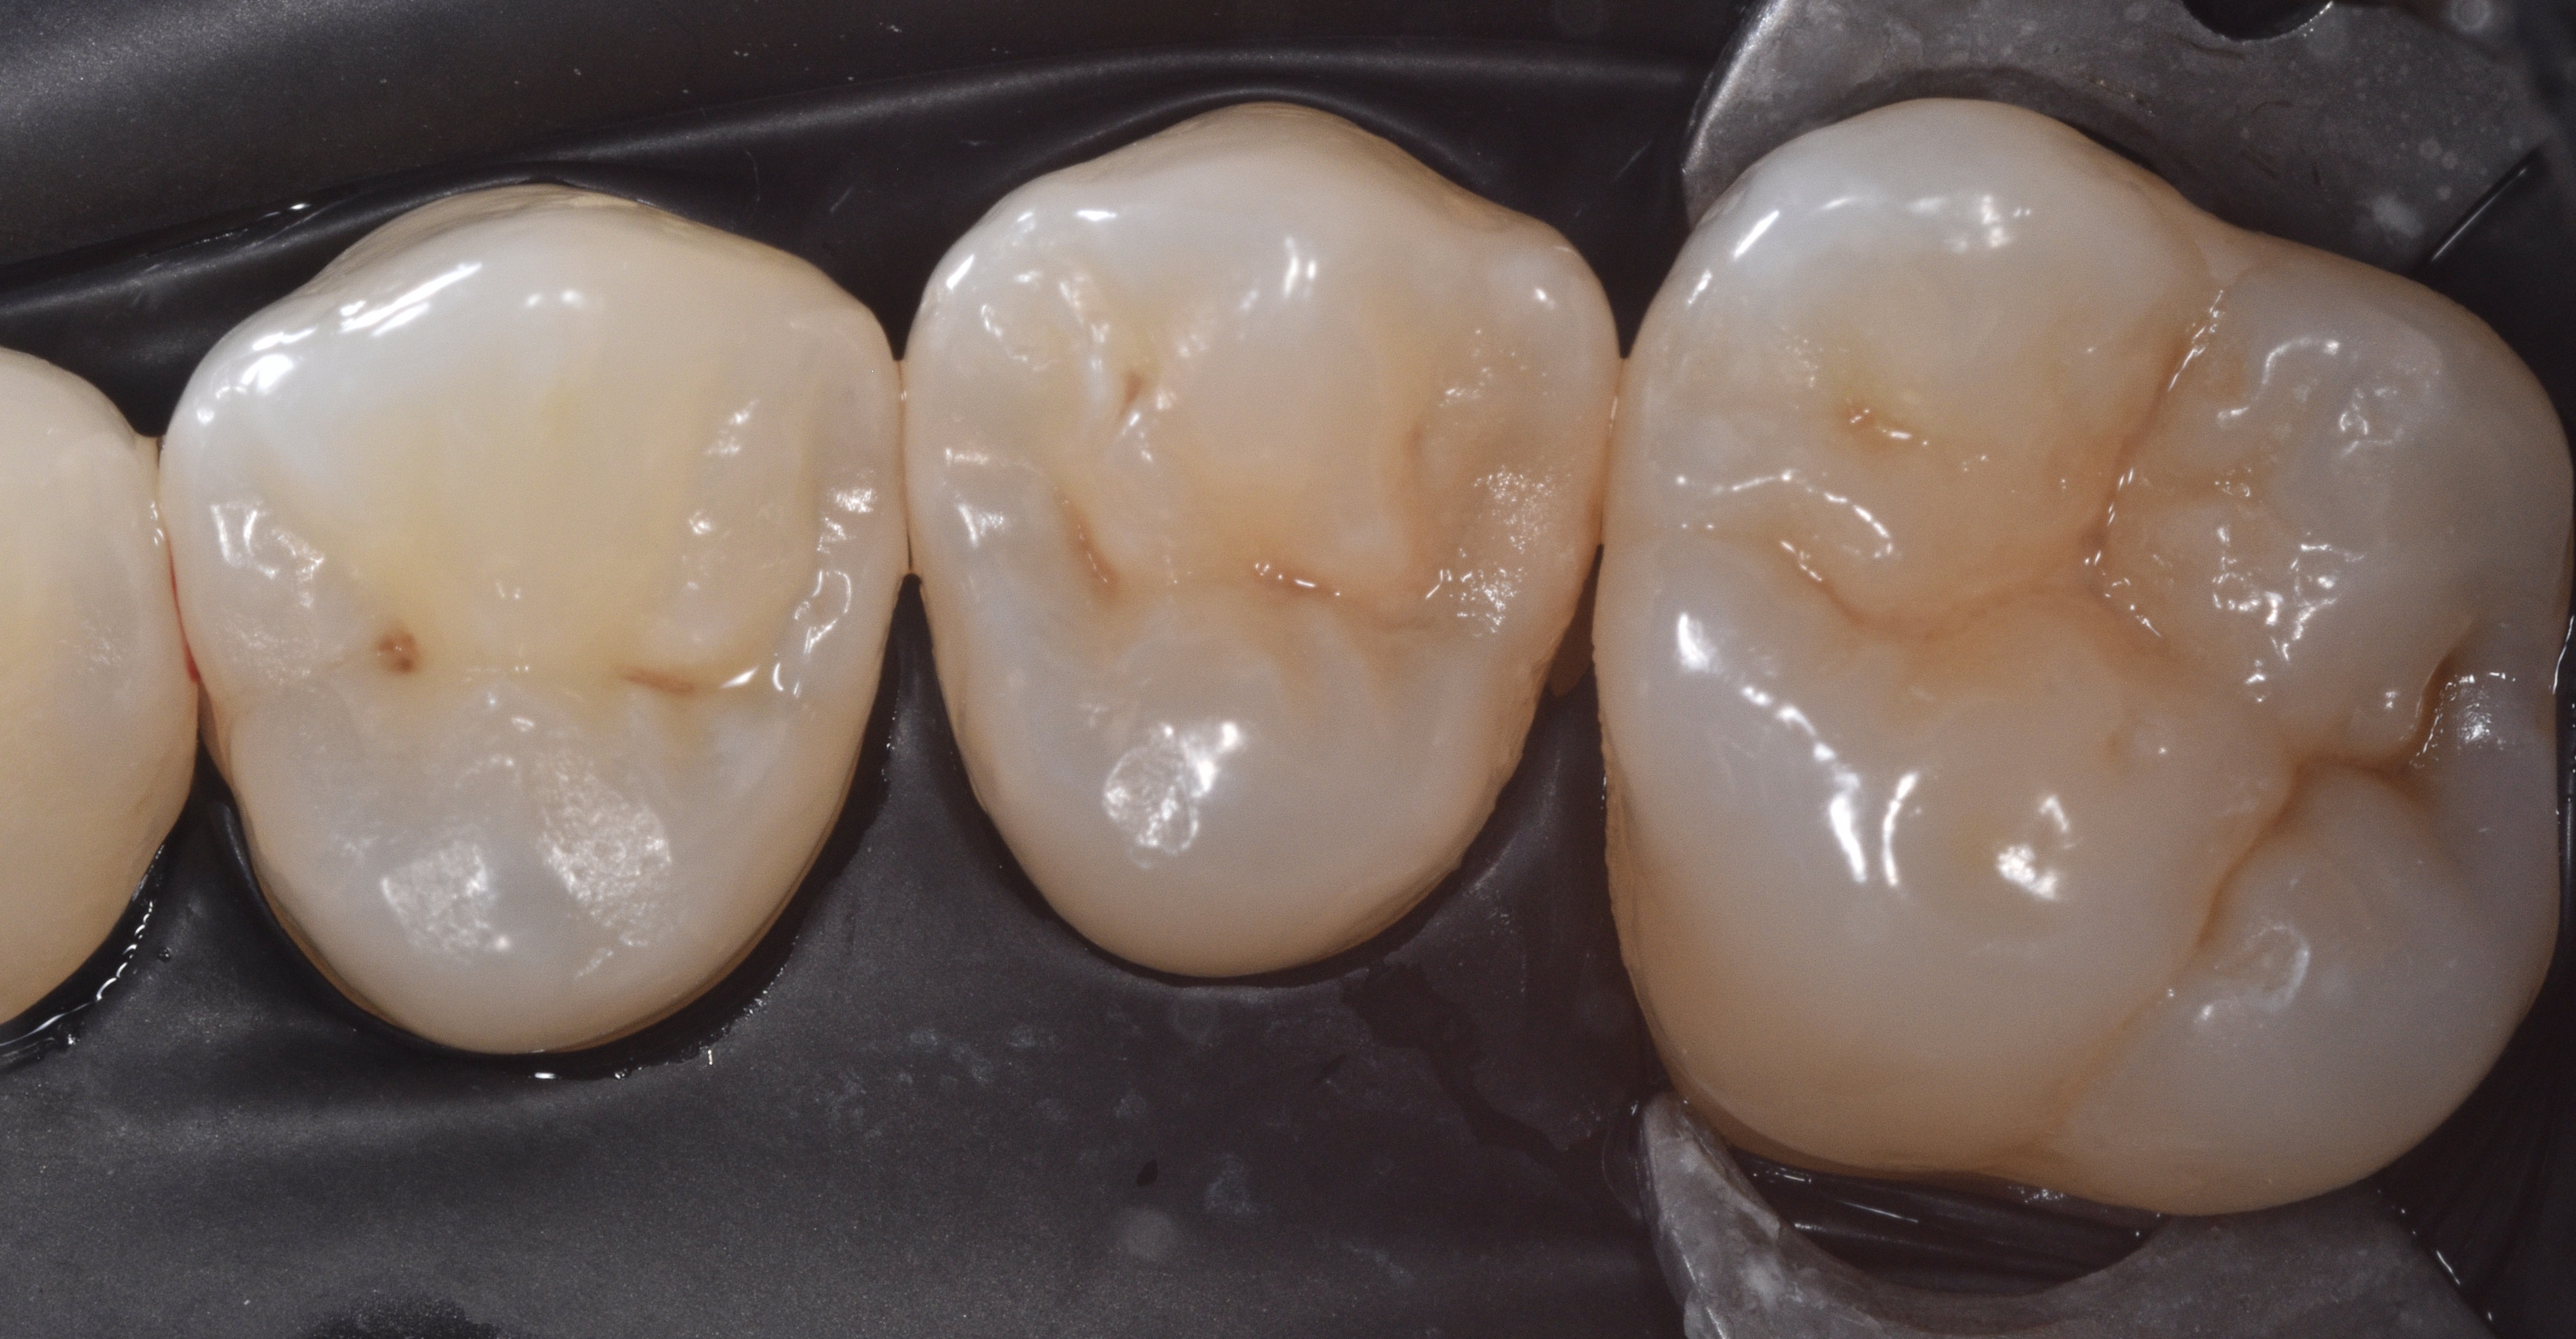

A 34-year-old female patient in good general health presented to my practice with interproximal carious lesions affecting teeth #12 on the distal-occlusal (DO) surface and #13 on the mesial-occlusal-distal (MOD) surface.

After profound anesthesia was accomplished using a carpule of OraBloc Articaine 4% with epinephrine 1:100.000 via infiltration, rubber dam isolation was completed (Black Hysolate-Coltene) (Figure 1)